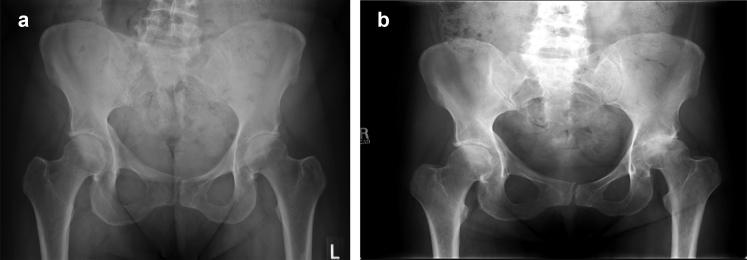

髋关节快速破坏性骨关节炎与关节内注射类固醇的关联。

Association of rapidly destructive osteoarthritis of the hip with intra-articular steroid injections.

To assess the relationship between rapidly destructive osteoarthritis (RDOA) of the hip and intra-articular steroid injections.

METHODS

Coding records from 2000 to 2013 were used to identify all subjects who had a fluoroscopy-guided intra-articular hip injection to treat pain associated with primary osteoarthritis. Radiographic measurements from preinjection and postinjection imaging were evaluated with Luquesne's classification of RDOA to determine diagnosis (greater than 50% joint space narrowing or greater than 2 mm of cartilage loss in 1 year with no other forms of destructive arthropathy). Demographic information, health characteristics, and number of injections were collected and analyzed as other potential explanatory variables. Patient outcome assessed by need for total hip arthroplasty (THA) after injection was also recorded.

RESULTS

One hundred twenty-nine injection events met the inclusion criteria in a total of 109 patients. From this sample, 23 cases of RDOA were confirmed representing a 21% incidence of RDOA. Twenty-one of the patients (91%) with RDOA had a THA at a median time of 10.2 months (interquartile range: 6.5-11.2) compared with 27 (31%) of those without RDOA at a median time of 24.9 months (interquartile range: 15.3-65.3). Older patients, patients with more severe osteoarthritis, and patients who identified themselves as white were more likely to have a diagnosis of RDOA ( = .008;  = .040;  = .009, respectively).

CONCLUSIONS

The potential for RDOA and faster progression to THA raises questions about the use of intra-articular steroid injections for hip osteoarthritis and should be discussed with patients. Additional studies are needed to define a true relationship.